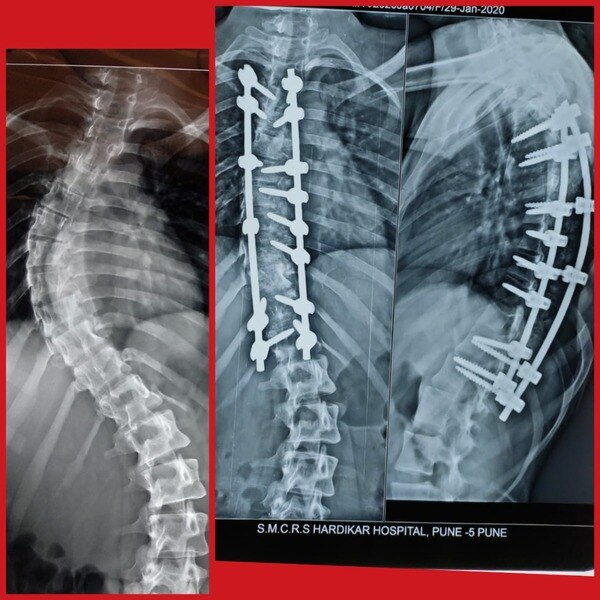

Dr. Rahul Chaudhari is a Reliable and Best Spine Surgeon, Spine Doctor, Spine Specialist in Bavdhan, Pashan, Sus, Bhugaon and Pune. Dr. Rahul Chaudhari is the USA trained Orthopaedic Spine Surgeon in Pune. He completed his MBBS/MS from KEM Hospital, Mumbai. He had received advanced spine/scoliosis surgery training in America for 3 years. His expertise involves treating cervical, thoracic, and lumbar spine disorders including degenerative spine conditions (slipped disc, sciatica, and spinal stenosis), fractures, tumors, and spinal deformities. He successfully treated many happy patients in his 17 years of journey as an Orthopedist.